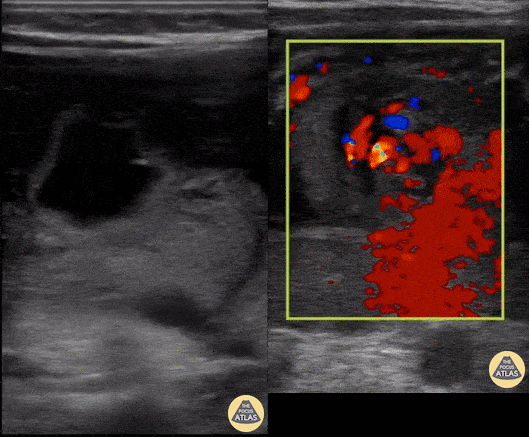

A 6-day-old presented with findings suggestive of volvulus. POCUS revealed whirlpool sign, consistent with midgut volvulus. The sign corresponds to a clockwise wrapping of the superior mesenteric vein and the mesentery around the superior mesenteric artery (augmented with color doppler in the image on the right). Michael Cooper